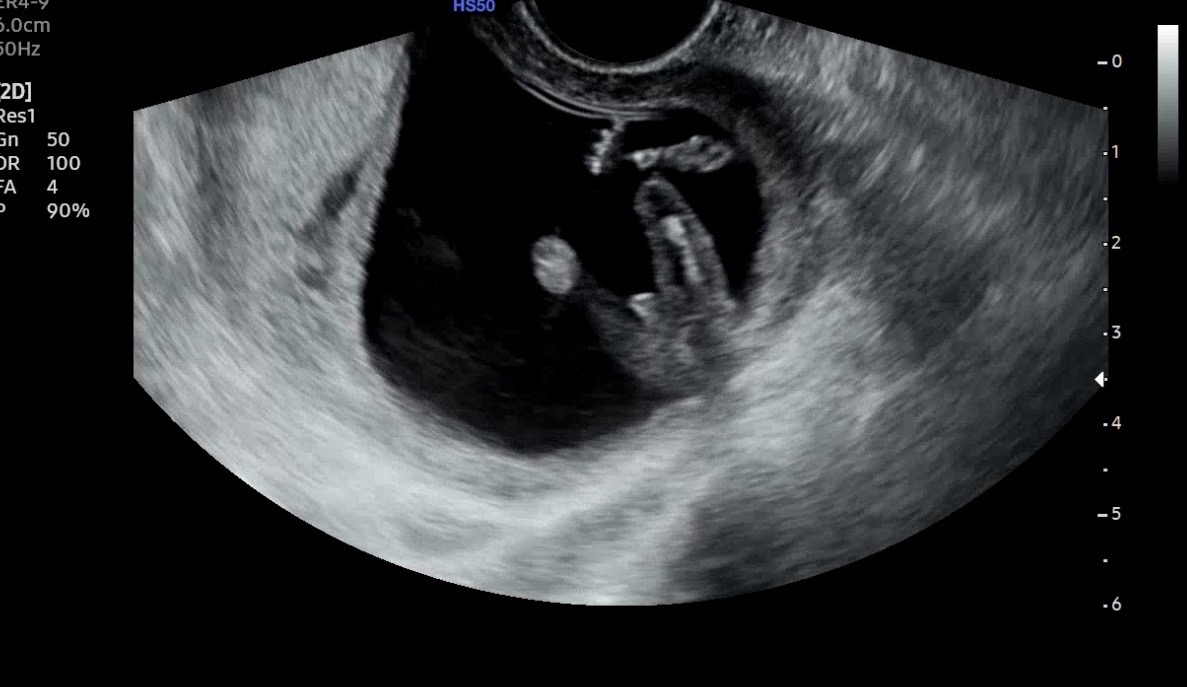

빼박 아들같나용

아들!!같나용

12주차 입니당

네 아들이시네요~~